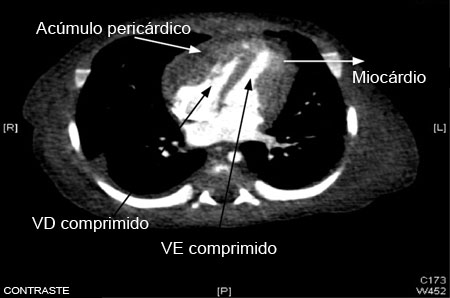

[Figure caption and citation for the preceding image starts]: Tomografia computadorizada (TC) do tórax em um bebê com pericardite purulenta, mostrando uma coleção pericárdica com compressão dos ventrículos esquerdo (VE) e direito (VD)Karuppaswamy V, Shauq A, Alphonso N. BMJ Case Reports 2009; doi:10.1136/bcr.2007.136564 [Citation ends].